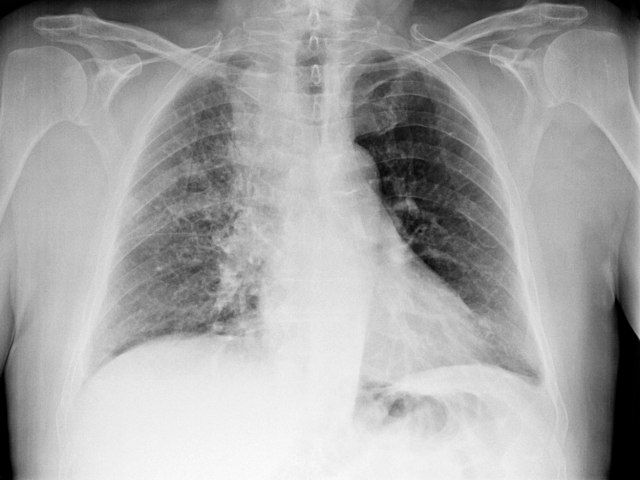

Prve simptome raka pluća vezujemo za manje ozbiljnu, akutnu bolest – znaci koje ne treba ignorisati

Rak pluća je fatalna bolest, ali ako se rano dijagnostikuje, može ozbiljno da poveća šanse za izlečenje.

Foto: Profimedia

Kod ljudi sa karcinomom pluća simptomi se ne javljaju često dok stanje nije dostiglo kasniju fazu bolesti.

Međutim, neki ljudi mogu primetiti simptome za koje misle da su povezani sa manje ozbiljnom, akutnom bolešću.